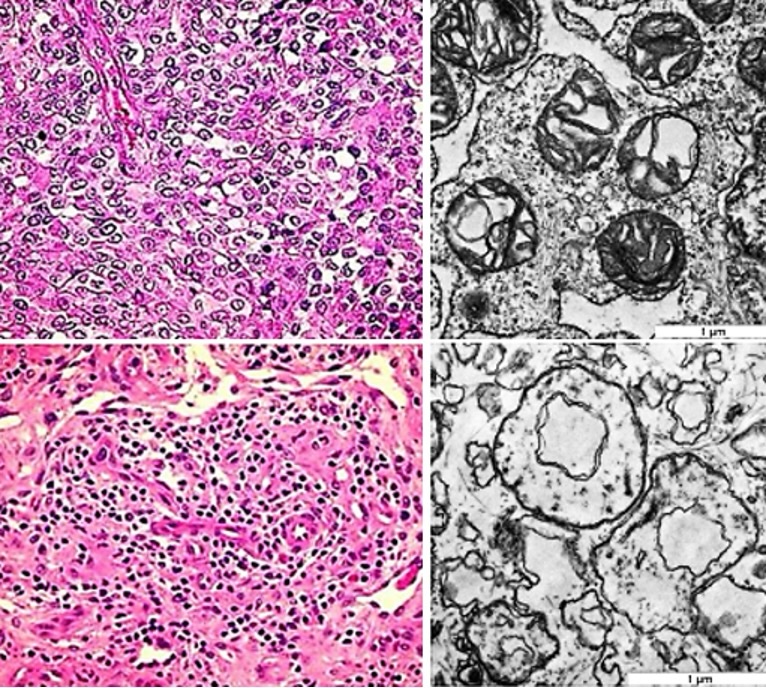

For evaluation of the TMI treatment effect in the tissue context, human surgical samples of cutaneous malignant melanoma were treated with 1, 000 and 2000 shock waves, respectively, at a frequency of 4 Hz with an energy flux density of 0.35 mJ/mm2. The effect was evaluated in light microscopy, and for cell membranes and intracellular structures, including mitochondrial and endoplasmic reticulum membranes, in transmission electron microscopy.

Human melanoma tissue. In light microscopy of treated human melanoma tissue, the most conspicuous change was an allover karyopyknosis indicating apoptosis. In electron microscopy, cell membranes and especially membranes of mitochondria and endoplasmic reticulum treated with 1, 000 shock waves were disrupted, and applying treatment with 2000 shock waves conspicuously affected by strain (Fig. 9). Further, a series of exposures of BLM cells and FF 1699 fibroblasts to TMI shock wave treatment showed that in both cell lines a certain percentage of apoptotic impairment occurred (between 15 and 60% in BLM cells, between 15 and 40% in FF1699 cells) dependent on different pressure shock frequencies (3 Hz and 4 Hz) and energy flux density (0.25 and 0.35 mJ/mm2), and especially on the number of shock waves applied (500, 1, 000, 2, 000 and 4, 000).

Fig. 9: Left: Untreated surgical sample of cutaneous malignant melanoma (above) and treated tissue (below) exhibiting pyknotic nuclei and eosinophilic changes of the fibrous matrix indicating apoptotic impairment (hematoxylin-eosin staining). Right: Ultrastructural disruption of BLM melanoma cells treated with 1,000 shock waves (above) and severe alterations after 2,000 shock waves (below) at 4 Hz with an energy flux density of 0.35 mJ/mm2 . The mitochondria are disrupted, the membrane strain increasing with the number of applied shock waves (transmission electron microscopy).